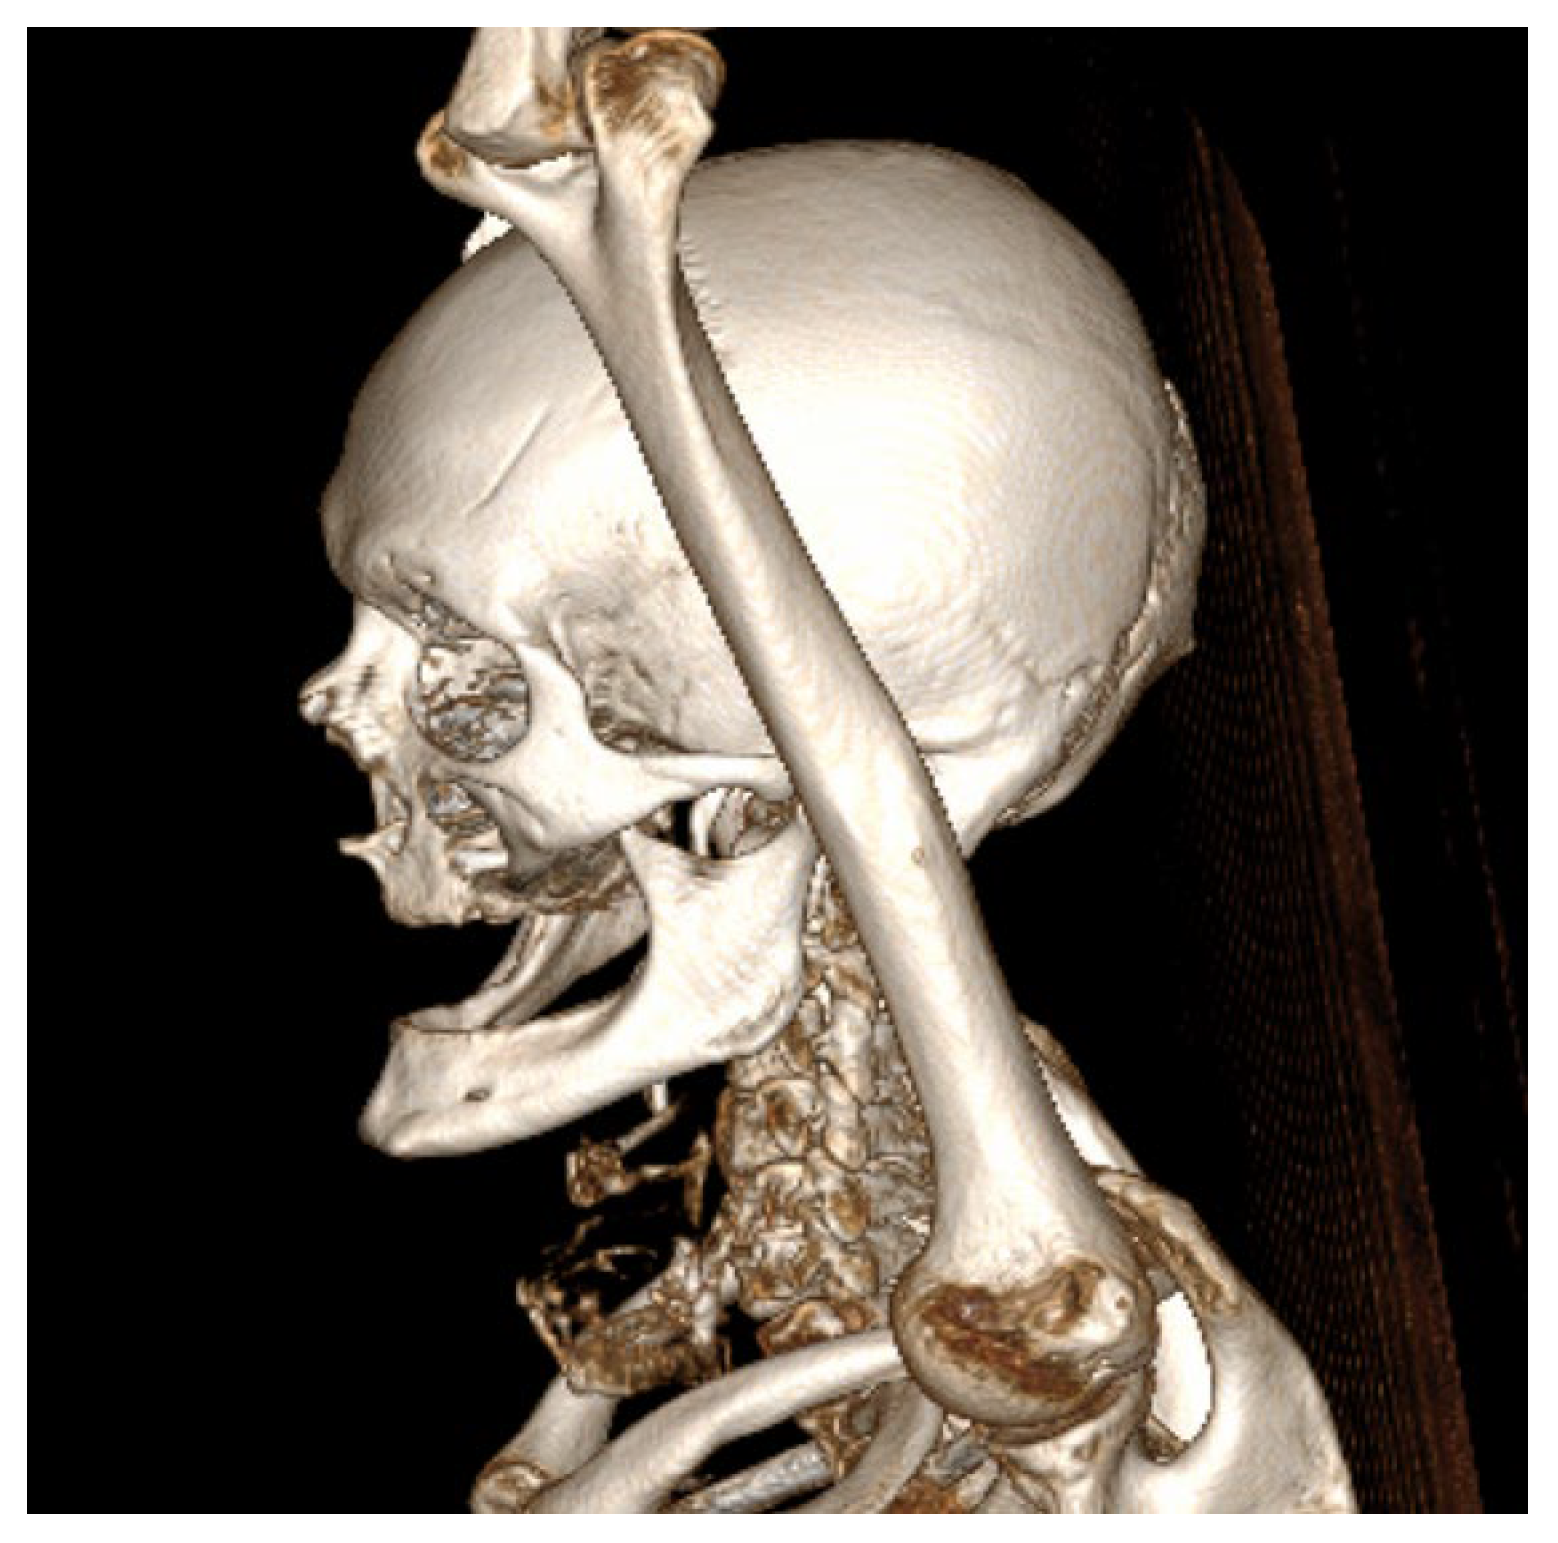

Figure 4.

Three-dimensional CT reconstruction in left lateral view demonstrating the craniofacial skeleton, cervical vertebrae, and upper thoracic cage with no bone destruction.